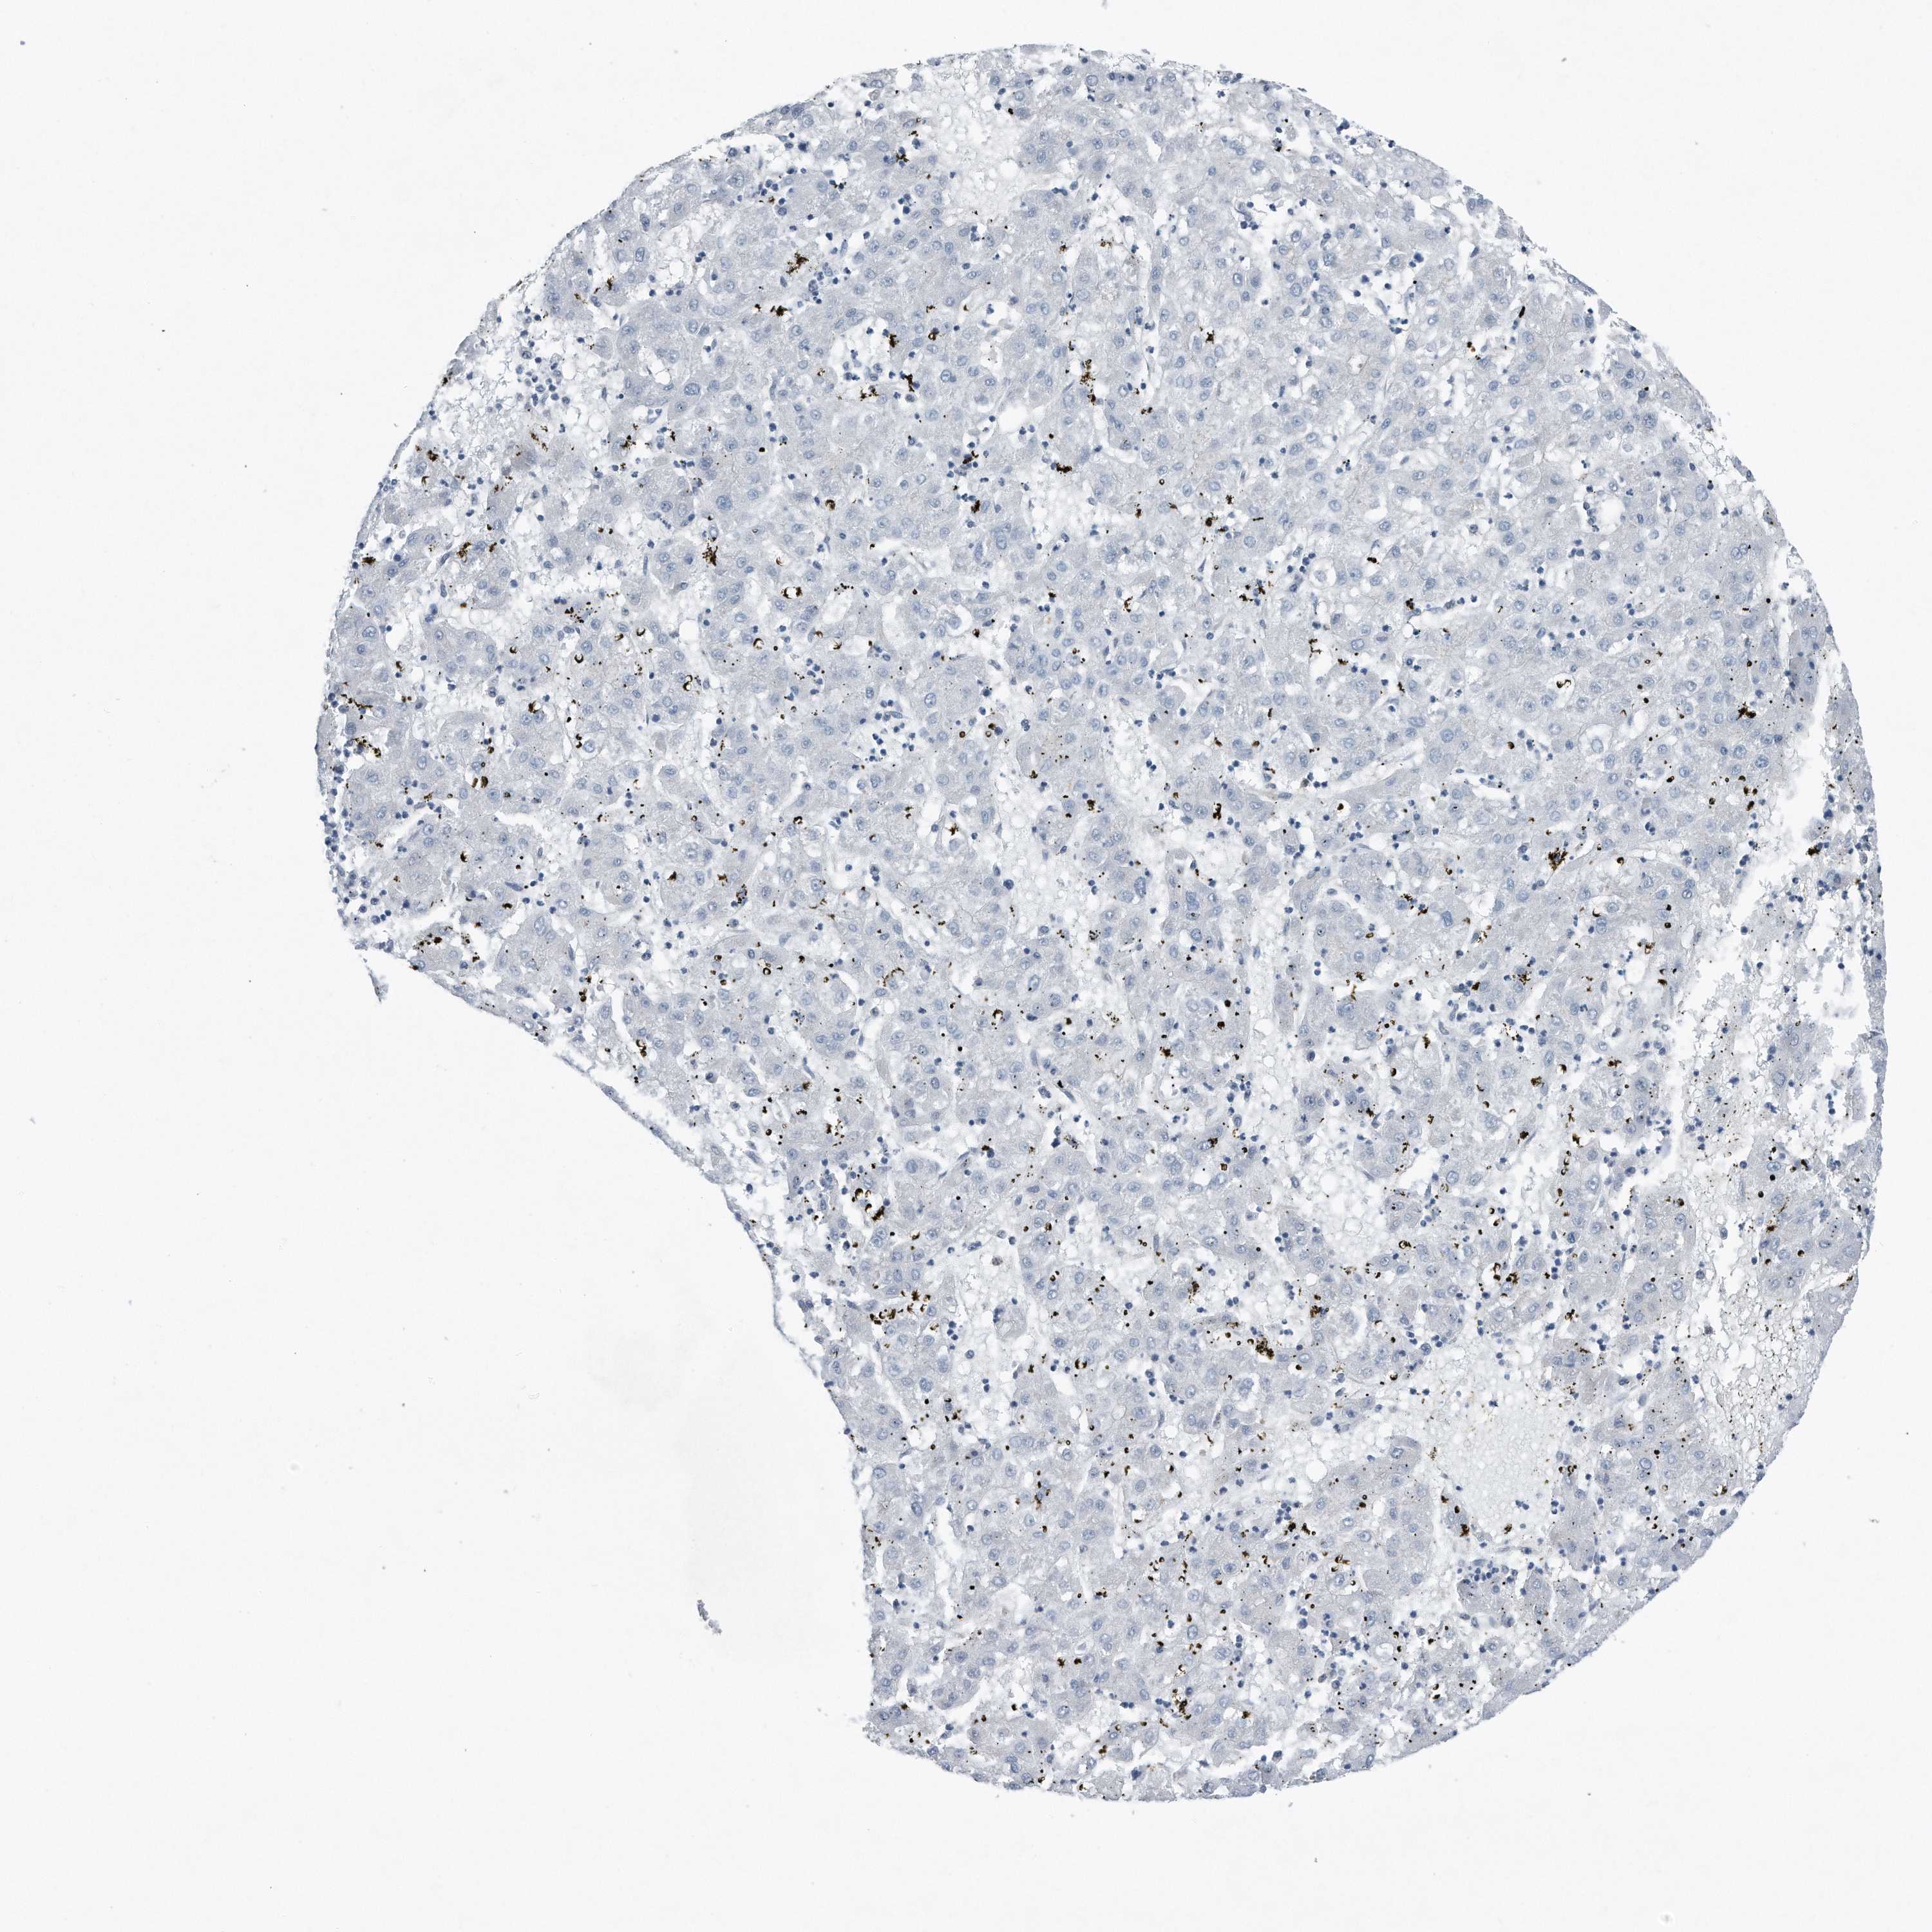

LIVER CANCER - Protein expressioni

A mouse-over function shows sample information and annotation data. Click on an image to view it in a full screen mode. Samples can be filtered based on level of antibody staining by selecting one or several of the following categories: high, medium, low and not detected. The assay and annotation is described here.

Note that samples used for immunohistochemistry by the Human Protein Atlas do not correspond to samples in the TCGA dataset.

Antibody stainingi

Antibody staining in the annotated cell types in the current human tissue is reported as not detected, low, medium, or high, based on conventional immunohistochemistry profiling in selected tissues. This score is based on the combination of the staining intensity and fraction of stained cells.

Each image is clickable and will lead to virtual microscopy that enables deeper exploration of all samples and also displays staining intensity scores, fraction scores and subcellular localization as well as patient and tissue information for each sample.

Antibody HPA030147

Staining

High

Medium

Low

Not detected

Intensity

Strong

Moderate

Weak

Negative

Quantity

>75%

75%-25%

<25%

None

Location

Nuclear

Cytoplasmic/membranous

Cytoplasmic/membranous,nuclear

Cholangiocarcinoma

Carcinoma, Hepatocellular, NOS